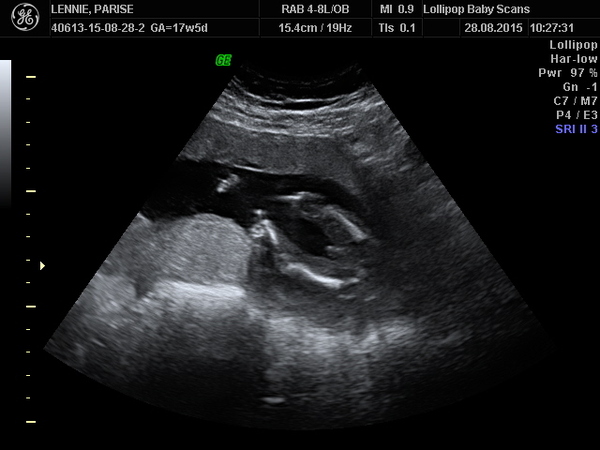

I went for a private gender scan last weekend, my guestimation was that i was 17 + 5 on the day (i've not actually had my dating confirmed by the midwives as every time they've gone to do the dating scan baby has been standing on its head Hmm) ANYWAY, she told me it was a boy within seconds however i've been doing some googling & if i'm less prego than i expected the bits look very similar.

I've attached a few pictures that she burnt onto a CD for me, i was just wondering if anyone thinks this looks 100% like i penis. I've already bought 37 blue baby grows so i'm kind of screwed if he comes out a girl HABlush.

I do have my "20 week" scan on the 8th, but im too impatient. Thanks guys :)